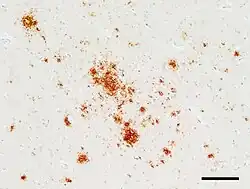

The degenerative tissue damage caused by prion disease in the nervous system is characterised by four features: spongiform change (the presence of many small vacuoles); the death of neurons; astrocytosis (abnormal increase in the number of astrocytes); and deposits of abnormal PrP (some of which have the characteristics of amyloid).[26] These neuropathological features have formed the basis of the histological diagnosis of prion diseases for many years, although it has been recognized that these changes are highly variable both from case to case and within the central nervous system in individual cases.[27][26] In humans, prion diseases with different genetic or infectious causes often have different patterns of pathology. For instance, amyloid plaques are rare in most prion diseases, but they are common in some diseases such as kuru and variant CJD. Owing to the rarity of amyloid per se in prion diseases, it is thought that non-amyloid forms of PrPSc are responsible for neurodegeneration.[26] In rare instances of human prion disease, tauopathy resembling the neurofibrillary tangles in Alzheimer's disease is present, highlighting the many ways in which the pathology of prion diseases can vary.[26] Despite this variation, all prion diseases have in common the buildup of abnormal PrP in the nervous system.